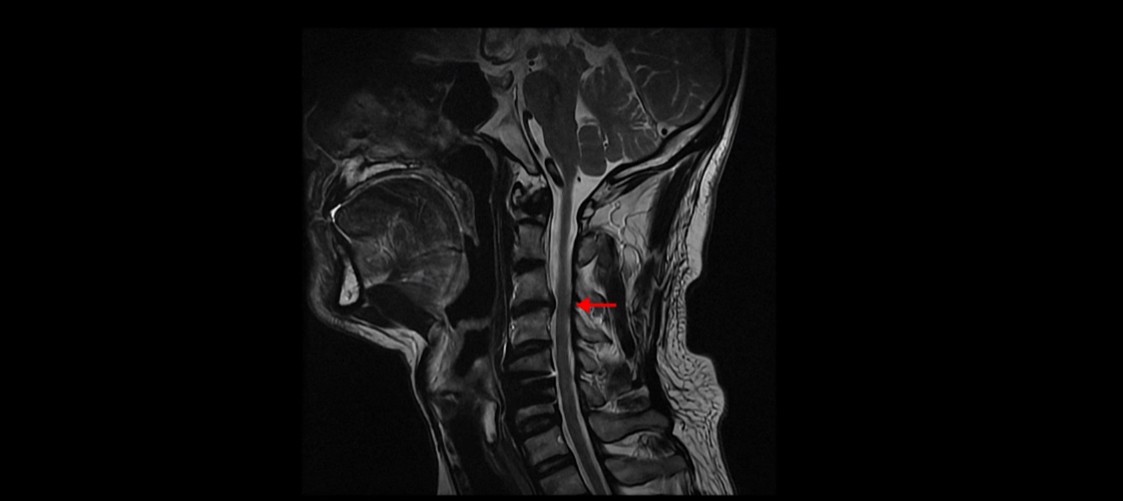

저희 모커리한방병원에서는 목이든 허리든 수술이 잘 됐다는 데도 계속 아프다면 당연히 근육 문제를 의심하고 치료해야 한다고 그렇게 반복해서 설명하는데도 신경 주사만 맞거나 아니면 치료를 포기하거나 아니면 추가적인 수술을 받는 분들도 있습니다. 이 환자분도 보시다시피 목의 다른 마디에도 퇴행성디스크와 협착이 있습니다.

이 환자분의 증상인 목, 어깨, 등 통증, 두통, 어지럼증, 눈 불편함, 시력 저하 이런 증상들은 원래가 목 근육 문제와 매우 밀접하게 관련된 증상들입니다. 저희가 목디스크, 목협착 환자의 99%는 거북목 환자라고 말씀드렸습니다. 이런 증상들은 거북목과 매우 밀접한 관련이 있습니다.

이런 목의 형태를 가지고 있으면 만성적으로 목과 어깨가 아플 가능성이 높습니다. 앞으로 밀려나간 머리를 목 근육이 붙잡고 있어야 하기 때문에 목, 어깨 근육이 뭉치면서 아프기 쉽습니다. 또 목 근육과 머리 뒤쪽 근육이 연결되어 있으므로 목 근육이 뭉치면 머리 근육도 뭉치면서 두통도 생길 수 있습니다. 또한 거북목은 목 앞쪽 근육이 짧아지면서 심하게 뭉치는데, 이 목 앞쪽 근육 사이로 얼굴 쪽으로 가는 수많은 신경과 혈관이 지나갑니다. 그래서 신경과 혈관이 영향을 많이 받기 때문에 어지럼증, 눈 통증, 눈 침침함, 이명 같은 증상이 생길 수도 있습니다.

목디스크의 제일 중요한 증상은 한쪽 손과 팔, 어깨 특히 견갑골 쪽 통증과 저림 증상입니다. 앞서 말씀 드린 그 외의 여러 증상들은 목 근육 문제와 매우 밀접한 관련이 있습니다. 그래서 목디스크 수술 후 한쪽 손, 팔, 어깨 저림 증상이 없어졌다고 해도 이런 다른 여러 복합 증상들은 좋아지지 않을 수도 있고 또 목 근육 문제로 인한 이런 여러 증상들을 목디스크 증상으로 오진했을 수도 있습니다.